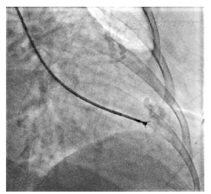

术中:吸氧、监测心律、心率、血压和血氧。常规消毒铺巾,应用改良Seldinger法穿刺右桡动脉,置入6F桡动脉鞘管(Cordis 6F Transradial Kit,经鞘管给予肝素5 000单位。根据病情及适应证决定是否同时行冠状动脉造影(coronary angiography,CAG)、肾动脉造影等。将Pigtail导管送入左心室,左心室造影图像设置为参考图像以备心肌活检时使用[右前斜30°和(或)左前斜60°],保留交换导丝于左心室内,撤回Pigtail导管,送入6F指引导管(Cordis Adroit 6F JR 4.0)注射少许造影剂,确定导管端孔于心室腔而未抵住心室壁,导管头端距离心室壁以2~3 cm为宜,距离室壁过近容易导致穿孔,距离太远会增加二尖瓣腱索损伤的风险。用肝素盐水纱布擦拭心内膜心肌活检钳[JAWZ Forcep,biopsy/105 cm/1.8 mm(0.070"O.D.)Jaw Dia./Straight/Stainless Steel/6F],在X线透视下,经指引导管送入活检钳,将其送至左室心尖或左室外侧壁,透视下调整活检钳位置,回撤活检钳约1.0 cm,张开钳口,重新将活检钳前送,一旦感到阻力快速闭合钳口,平稳回拽活检钳使其脱离左心室壁(图1),在活检钳撤出时保证钳口处于闭合状态。活检钳退出指引导管后,回抽并用肝素盐水冲洗指引导管。分别于室间隔、左心室侧壁或左心室前壁钳取心肌组织4~6块,每次取出标本后以无菌针头将其立即剔入10%福尔马林溶液(光镜检查)或2.5%戊二醛溶液(电镜检查),两次活检操作间期用肝素盐水冲洗指引导管,并用肝素盐水清洗活检钳。心肌活检结束后,重复左室造影,判断有无造影剂进入心包腔或右心室。操作结束后,拔除桡动脉鞘管,局部加压包扎。操作流程见图2。

张开钳口,前送活检钳,感到阻力快速闭合钳口,平稳回拽活检钳使其脱离左室壁(投照角度:右前斜30°)